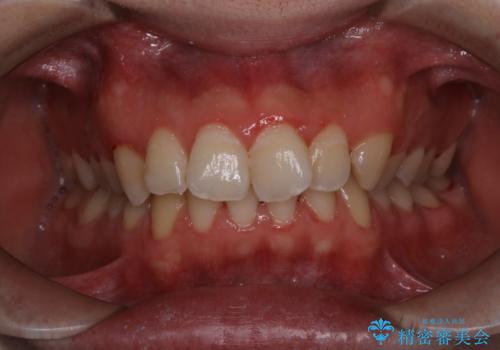

- 20代男性

- 1日

- 1回

- ¥11000費用は治療当時の料金となります